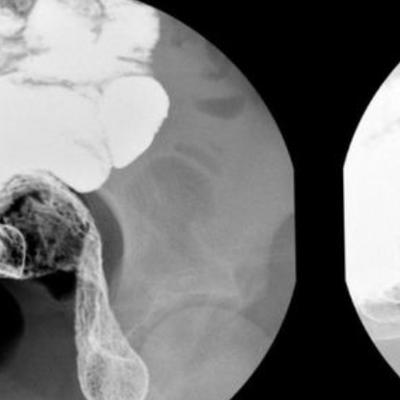

为了确认诊断,医生决定进行一系列的检查。首先,他给小明进行了体格检查,接着,医生安排了一次腹部X光检查。

很快,经过一番等待,医生终于拿到了X光片的结果。他仔细地观察着,发现小明的结肠上确实存在一个憩室,这个憩室是肠壁的一部分突出形成的。

随后,医生向尚女士解释说,患者是患上了梅克尔憩室症。